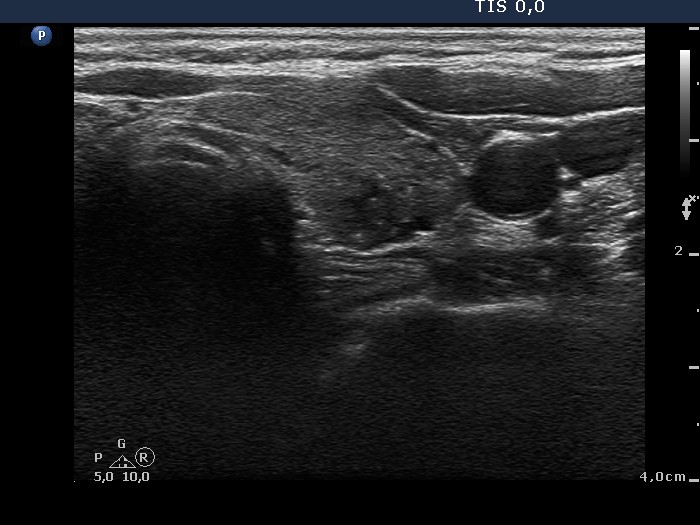

Ultrasonography: The thyroid was hypoechogenic. There was a small, more hypoechogenic area with blurred borders and a focus of microcalcification in the left thyroid.

Cytology was performed from the lesion in the left lobe and resulted in Hashimoto's thyroiditis.